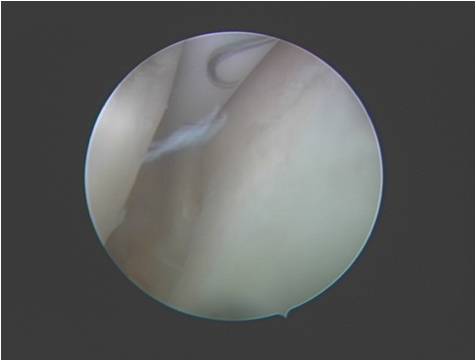

交叉韧带重建